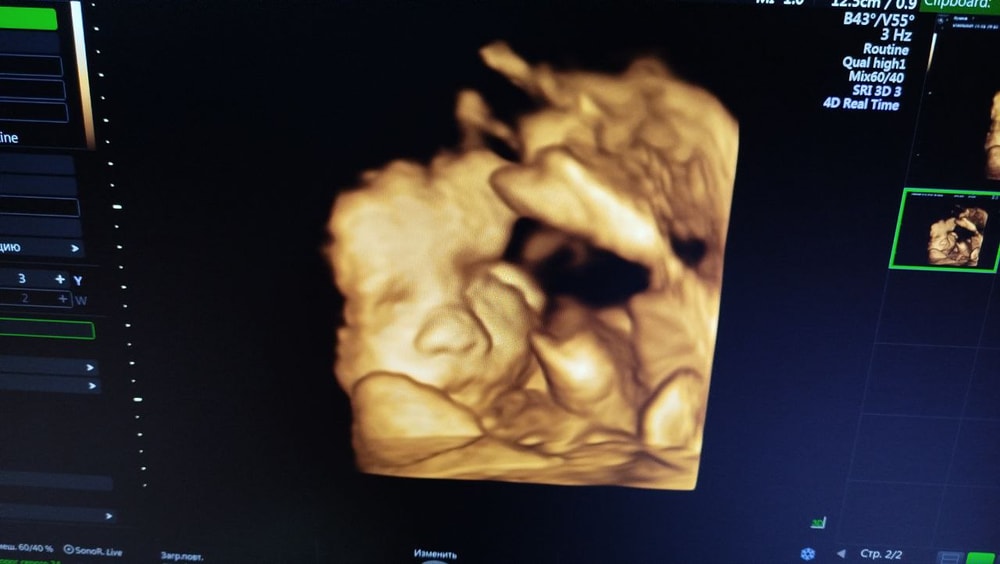

У нас на 26 неделе (нижнее фото) и 34 неделе получилось немного, и то врач аж всяко пыталась извернуть меня😀 а так тоже, если чуть замешкаешь, то всё, ручками закрывается, что правда начинаешь думать, что УЗИ им не приятно😒